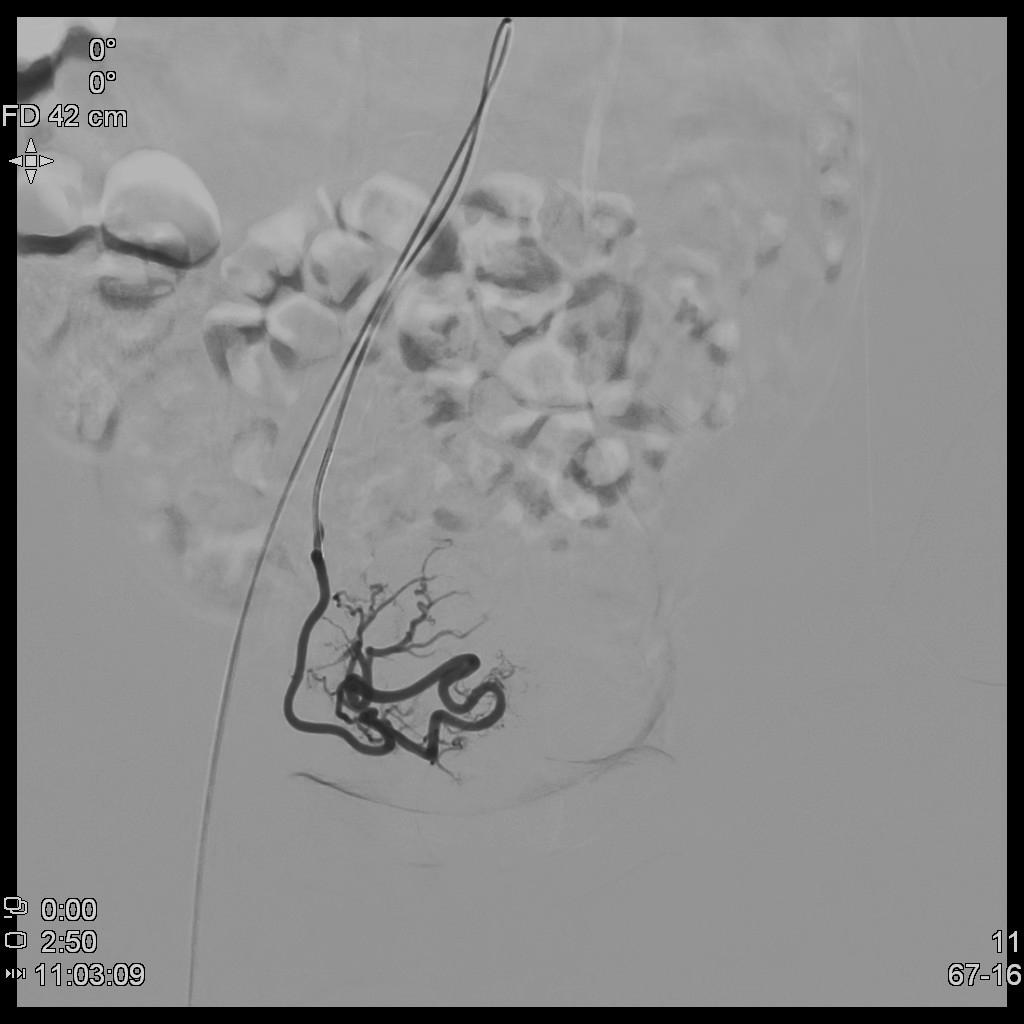

- 经左侧桡动脉穿刺置管,行腹主动脉造影显示双侧子宫动脉增粗、迂曲。

- 超选择插管右侧子宫动脉病灶供血动脉造影+栓塞治疗。

- 超选择插管左侧子宫动脉病灶供血动脉造影+栓塞治疗。